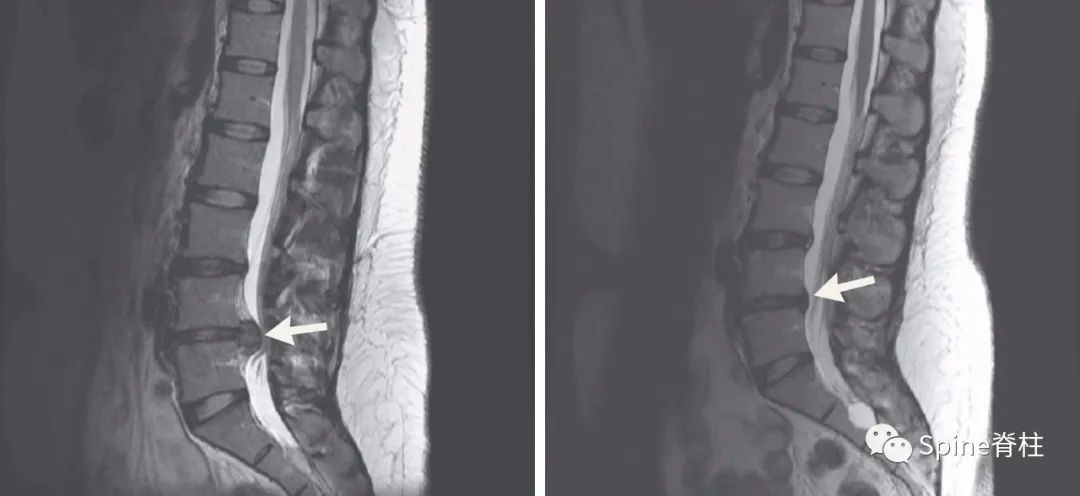

发表在顶级四大医学期刊之一的NEJM的最经典病例:患者为29岁女性患者,因“右小腿疼痛、感觉异常”就诊,大小便正常。起始腰椎磁共振提示腰4-5椎间盘突出并椎管狭窄,神经根压迫严重(左图)。她选择保守治疗,5个月后,复查腰椎磁共振惊奇的发现突出的椎间盘被吸收了,且临床症状完全缓解。